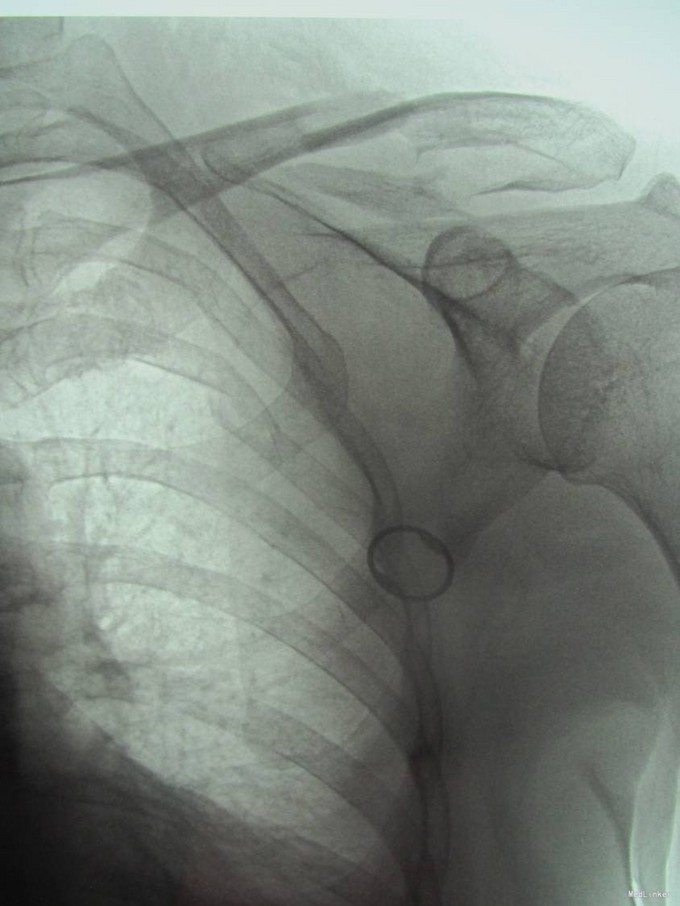

主诉:摔伤后左肩部疼痛活动受限18天 现病史:患者自述于2015-5-9日中午在沈阳市辽岛附近骑直行车时自己摔伤,左肩部着地,伤后患者左上肢疼痛活动受限,急诊送至沈阳市胸科医院,行左肩关节正位DR,提示为左锁骨骨折,患者于胸科医院保守治疗肋骨骨折13天,于2015-5-22日出院,现患者感觉左肩部疼痛,为求进一步治疗来到中国医科大学附属盛京医院创伤骨科,患者入科后神志清楚,饮食佳,无头晕头迷,无恶心呕吐,二便正常。

专科查体:患者左上肢吊臂带悬吊中,左肩关节肿胀,可见锁骨隆起,压痛(+),叩击痛(+),锁骨远端按压有浮动感,左上肢感觉正常,桡动脉搏动有力,末梢血运良